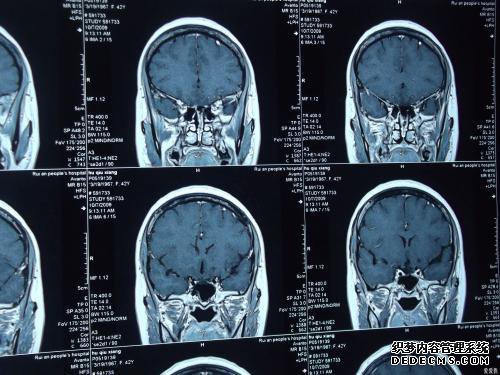

在马鞍上,看到the骨结构的阴影,T1WI是低信号,

上鞍池的垂体主干随后被扩大,局部囊性水样信号被认为是囊肿的原因。

检查报告是垂体腺不规则扩张,并在椅子内的椅子上显示“雪人标志”。

垂体瘤,鞍背平坦,下部略微向下推,椅子的形状像南瓜。

垂体的左侧有一种异常的圆形信号群落,T1WI是相同的信号/ T2WI。

对于垂体肿瘤,扫描显示垂体窝增大,并且椅子和椅子的内部空间可见。

鞍形没有任何异常的变化。椅子是空的,垂体组织被弄平并粘在椅子底部和大部分椅子上。